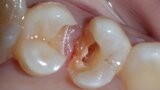

Predictable posterior restorations